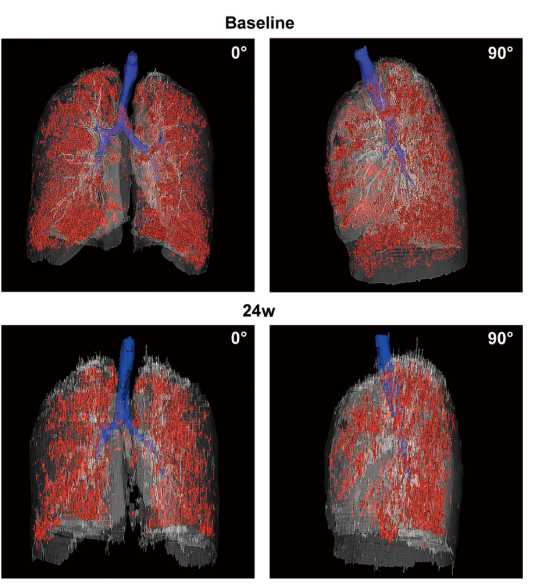

2024年2月14日,同濟大學醫學院附屬東方醫院在國際期刊《Translational Medical Sciences》上發布了一篇《P63 +肺祖細胞自體移植治療慢性阻塞性肺病》的研究結果。【2】

影像學檢查:對于患者 #2902,定量分析顯示基線時總體肺氣腫面積比為 12.75%,移植后 24 周降至 10.02%。在患者 #8009 中,肺氣腫面積比值從基線的 10.85% 下降到移植后 12 周的 9.08%。CT 圖像的三維可視化顯示,肺氣腫的減輕在下葉比在上葉更明顯。